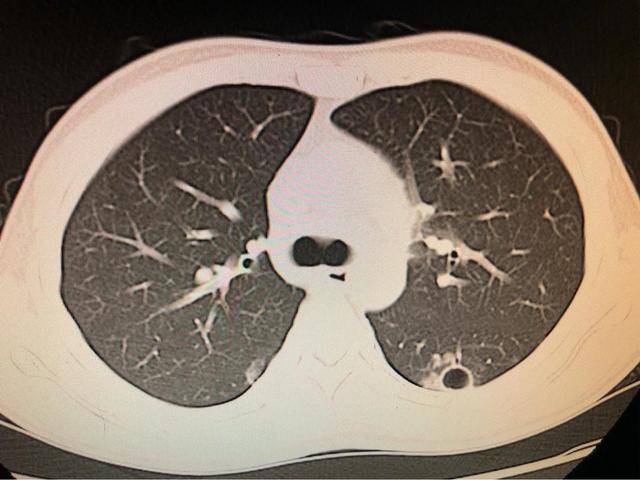

結核は結核菌の感染によって起こる慢性の感染症であり、結核菌は全身の様々な臓器に侵入するが、主に肺に侵入するため肺結核と呼ばれ、主に呼吸器を通じて感染する。微熱や倦怠感などの全身症状と、咳や喀血などの呼吸器症状がみられることが多い。一般に、咳や痰が2週間以上回復しない場合は、他の臨床検査、画像検査、検査項目と組み合わせて、結核と診断することができます。